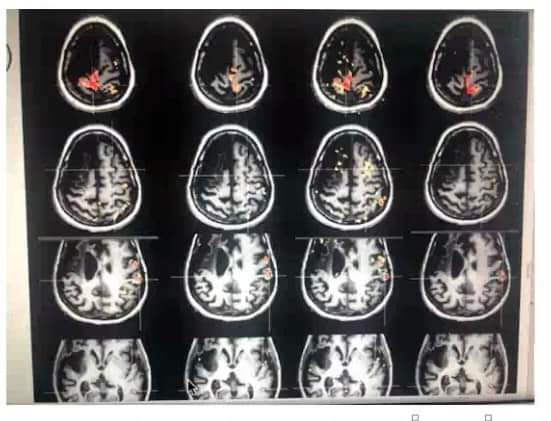

Fascinating recent research about how the brain lights up during a reflexology treatment …

As part of a medical school research project, thousands of brain scans were taken while participants received foot reflexology.

Neuroscientists were ‘blown away’ by the results, with the lead investigator saying the brain was ‘activated like a Christmas tree’.

What stumped the researchers most was that reflexology activated parts of the brain that have no direct connection to the feet!

Here’s a summary of the results from Kevin & Barbara Kunz who shared the findings in a webinar for reflexologists last week: